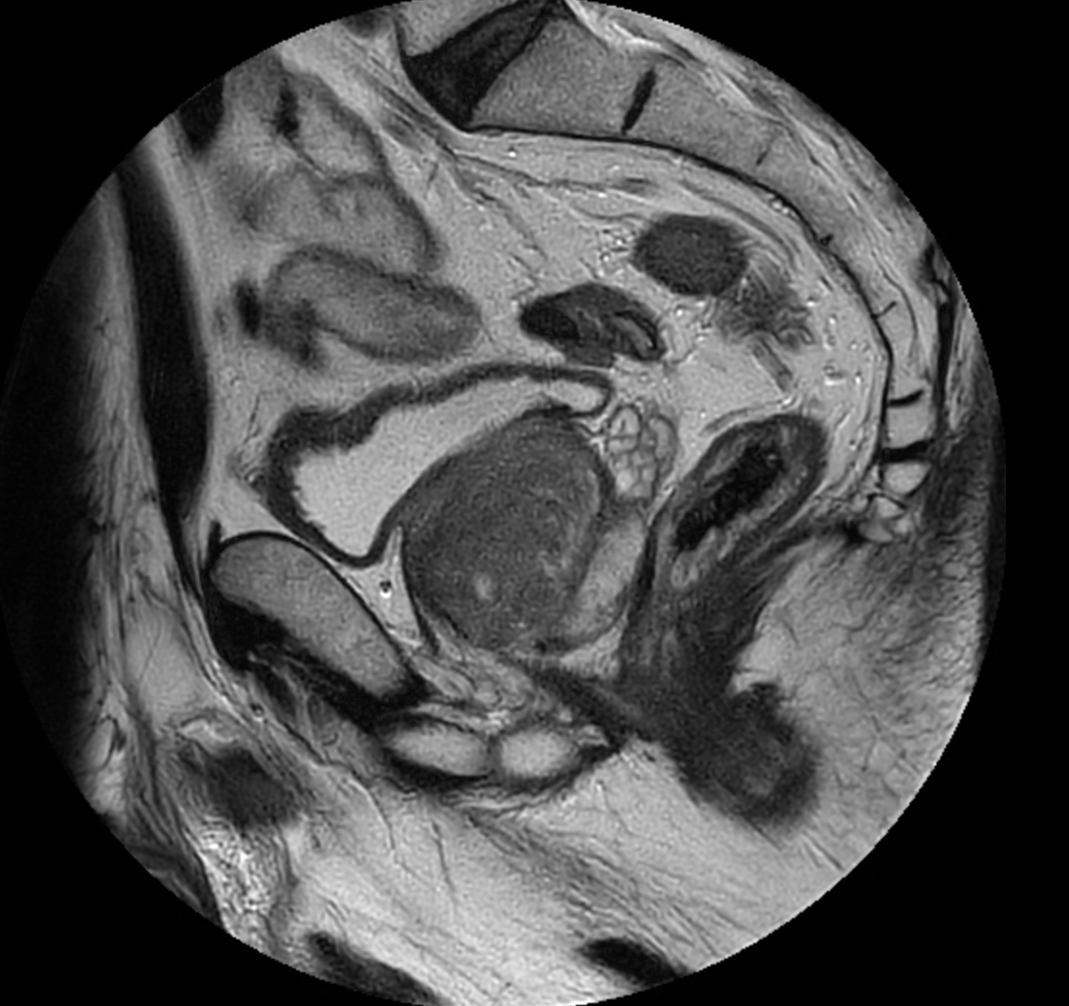

Sagittal T2w TSE - MultiVane XD